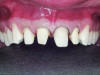

Figure 4. Bis-acryl mock-up.

Figure 4